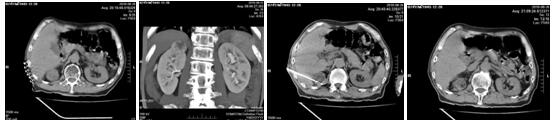

化療后病人一般情況尚可,經(jīng)過充分的術(shù)前檢查及準(zhǔn)備后,2018年6月26日在苗滿園主任的帶領(lǐng)下,與CT室聯(lián)合進(jìn)行手術(shù),局麻后在CT引導(dǎo)下將電極針準(zhǔn)確插入腫瘤內(nèi)部,對腫瘤實施微波消融術(shù)。僅20分鐘順利完成手術(shù),達(dá)到了預(yù)期的滿意效果和消融范圍。術(shù)中患者清醒無不適,術(shù)后6個小時患者即可下床活動。術(shù)后評估微波消融治療范圍,無出血及鄰近臟器損傷。